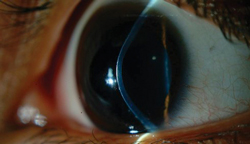

El queratocono es una alteración ocular en la que se produce un adelgazamiento progresivo de la zona central o paracentral de la córnea.

Queratocono avanzado.